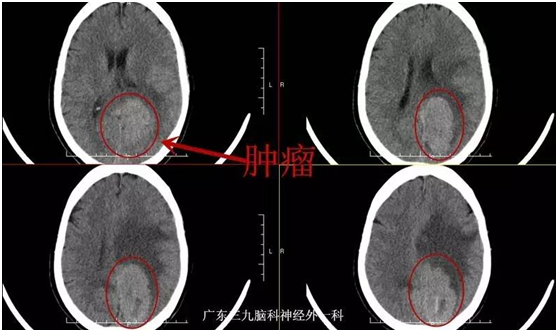

黄奶奶,72岁,因“视物模糊3个月,右侧肢体乏力半个月”入院。3个月前老奶奶无明显诱因下,出现左眼视物模糊,近半个月来出现右侧肢体乏力伴行走不稳,当地医院颅脑MR检查示:左侧枕叶镰窦旁占位性病变,门诊拟“左侧枕叶镰窦旁脑膜瘤”收入我院。入院视力1米数指。入院后完善相关检查,在全麻下行左侧枕叶镰窦旁脑膜瘤切除,手术后恢复良好,老奶奶视物较前改善,能下地行走。

视野缺损。甚至失明:脑膜瘤位于大脑后部时,可以引起视野改变,常未引起病人注意。检查可发现视野缺损。肿瘤常长到巨大体积时,巨大镰旁脑膜瘤可压迫双侧枕叶距状裂,造成失明。本例患者肿瘤正好压迫皮质视感觉区,出现视力严重下降。